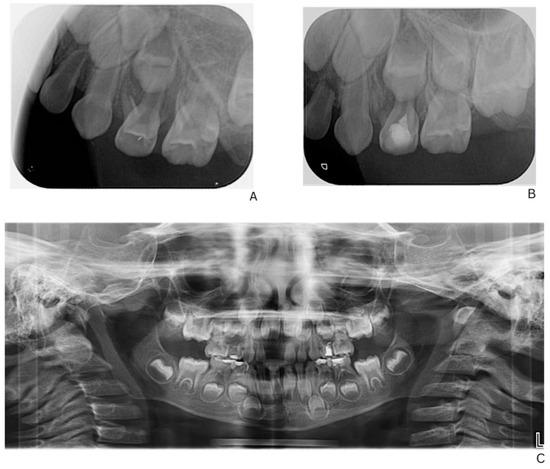

Early Dental Manifestations and Multidisciplinary Management of X-Linked Hypophosphatemic Rickets in a Pediatric Patient: A Case Report

by Nadezhda Mitova, Valentina Petkova-Ninova and Yana Popova

Children 2026, 13(1), 16; https://doi.org/10.3390/children13010016 - 20 Dec 2025

Abstract

Background: X-linked hypophosphatemic rickets (XLH) is a rare hereditary disorder characterized by renal phosphate wasting and impaired bone mineralization. Oral manifestations such as spontaneous periapical lesions and dental abscesses in the absence of caries or trauma may precede systemic features in XLH due [...] Read more.

Background: X-linked hypophosphatemic rickets (XLH) is a rare hereditary disorder characterized by renal phosphate wasting and impaired bone mineralization. Oral manifestations such as spontaneous periapical lesions and dental abscesses in the absence of caries or trauma may precede systemic features in XLH due to underlying dentin hypomineralization and enamel–dentin junction defects, and could serve as early diagnostic indicators. Case Report: We report on the case of a 4-year-old boy referred to our pediatric dental unit with recurrent intraoral fistulas persisting over the past year. Clinical examinations and an orthopantomogram revealed extensive root resorption and periapical pathology affecting multiple primary molars without evident caries or trauma. Laboratory investigations showed hypophosphatemia, elevated renal phosphate loss, and raised inflammatory markers (CRP (C-reactive protein) and granulocytes). Genetic testing of the child and his mother confirmed a diagnosis of X-linked hypophosphatemic rickets. Management: Due to behavioral challenges, treatment proceeded with difficulty over multiple visits. Endodontic treatment was initiated using a formalin–resorcinol technique; however, several primary molars developed progressive necrosis and required extraction. Orthodontic space maintainers were placed to preserve arch integrity and support future eruption. The patient remains under follow-up and is currently awaiting Burosumab therapy. Despite systemic management, spontaneous necroses of the primary molars persist, highlighting the refractory nature of dental involvement in XLH. Conclusions: This case underscores the pivotal role of pediatric dentists in recognizing systemic diseases through oral findings and demonstrates the challenges of managing XLH-related dental pathology, even under targeted systemic therapy. Early interdisciplinary collaboration is essential to optimize both dental and systemic outcomes in affected children. Full article

(This article belongs to the Section Pediatric Dentistry & Oral Medicine)

Show Figures

Figure 1